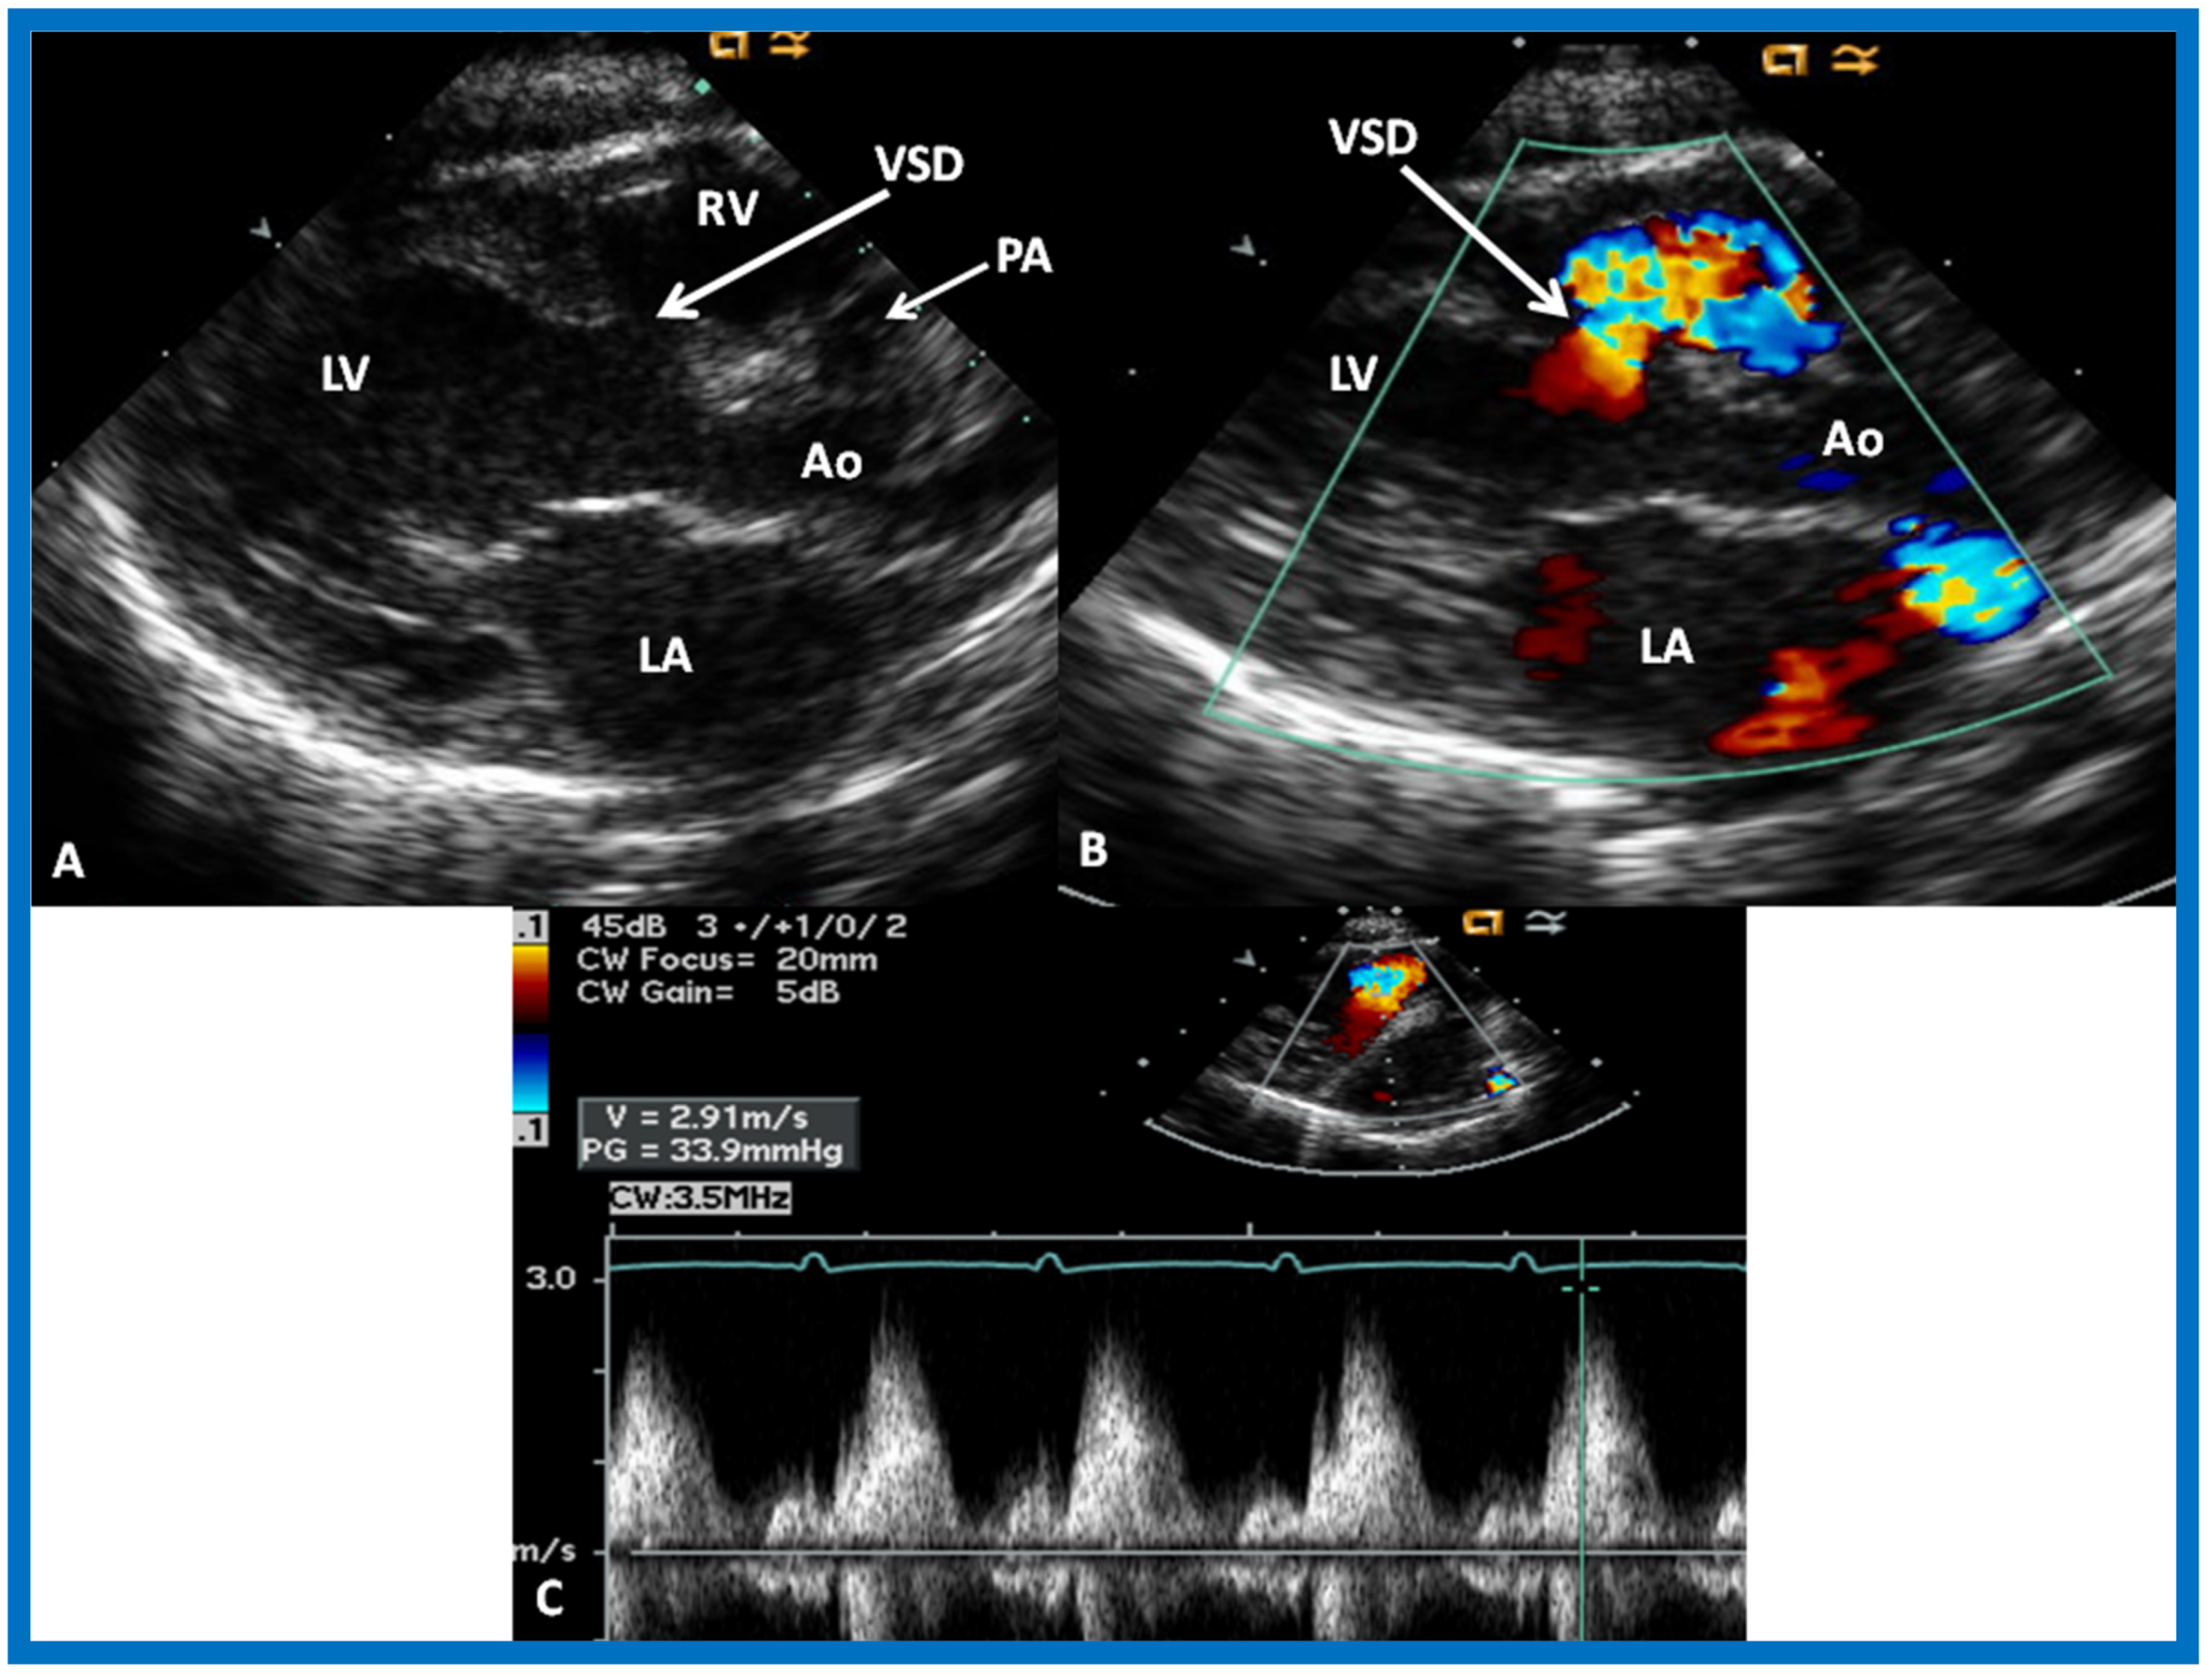

The relationship of the great arteries is examined next in order to classify them into various types [41]. The relationship of the great arteries is established by following the vessels arising from the ventricles until pulmonary bifurcation or aortic arch. In Type I patients with normally related great arteries, the aorta arises from the LV (Figure 20), while in Type II patients with transposition of the great arteries, the PA arises from the LV (Figure 21 and Figure 22). In Type III patients, it may be little more difficult to assign the great artery relationship, and sometimes angiography is needed. In type IV with truncus arteriosus, the limited data [22] suggest that this can be done by echocardiography (Figure 23 and Figure 24).

Figure 20.

Selected video frames from precordial long axis views of a neonate with tricuspid atresia with normally related great arteries demonstrating enlarged left atrium (LA) and left ventricle (LV), a small right ventricle (RV) and a moderate sized ventricular septal defect (VSD) (thick arrow) on 2D (A) and color flow (B) imaging. Turbulent flow (B) with a Doppler flow velocity of 2.91 m/s by continuous wave Doppler (C) suggests some restriction of the VSD. Ao, Aorta; PA, pulmonary artery. Reproduced from Rao P.S. [39].

Then, the ventricular septum is evaluated; the ventricular septum is intact in most Type Ia cases. In children with Type I (normally related great arteries), the VSD supplies pulmonary blood flow (Figure 20) while in patients with Type II (transposition the great arteries), the VSD allows blood to flow into the systemic circuit (Figure 21 and Figure 22). In Type I patients, the VSD is demonstrated by 2D (Figure 20A) and the left to-right shunt across it by color (Figure 20B), pulsed and CW (Figure 20C) Doppler signals. Interrogation of the right ventricular outflow tract and pulmonary artery region is performed; peak Doppler flow velocity across the right ventricular outflow tract and pulmonary valve is helpful in identifying obstruction across these sites. The Doppler data from the VSD and RVOT are also helpful in estimating of pulmonary artery pressures. In these Type I babies, the 2D size of the VSD and the peak Doppler flow velocity across it are useful in quantifying the size of the VSD (Figure 20); the higher the VSD Doppler velocity, the smaller the defect. However, in patients with pulmonary hypertension, severe infundibular or valvar pulmonary stenosis, the VSD Doppler velocities do not reflect the size of the VSD. Barring these exceptions, right ventricular and pulmonary arterial pressure may be estimated using modified Bernoulli equation (RV/PA systolic pressure = systolic BP − 4V2).